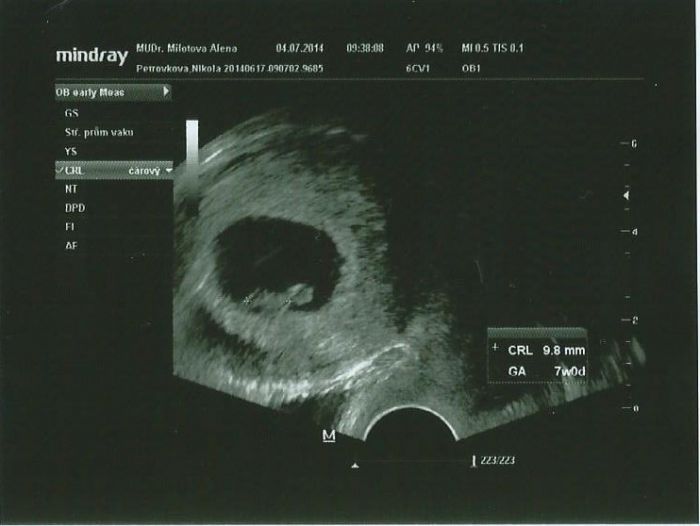

Ahojky holky tak jsem konecne doma :) tak vsechno vypada tak ja ma :) srdicko tlouklo o sto sest i jsem ho slysela :) CRL 9.8... Je to mrnousek ale je to uplne v poradku podle utz jsem 7+0, proste nam tam hapruje furt tech pet dnii :) ovu byla pozdeji :) :-* prikladam foto naseho drobecka :) to kulate neni hlava :D ale zloudkovy vacek :D Kdyz jsem to videla na utz tak jsem se ptala kde vzal takovou velkou hlavu :D:D .. Kati cekam na tve dobre zpravy :)